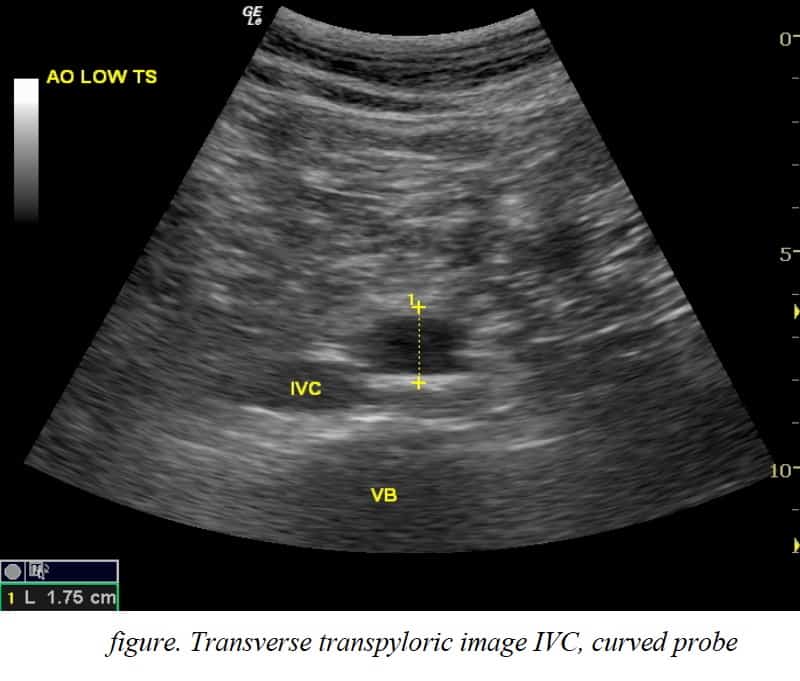

3 IVC Ultrasound Prereading for FCUS Course Intensive Care Network